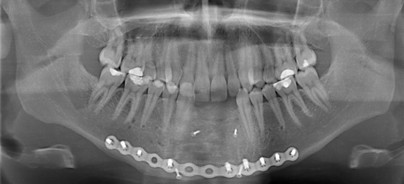

Am 29.06.2008 wurde der Patient nach einem Sturz aus zwei Meter Höhe an der Unfallabteilung im LKH St. Pölten erstmals begutachtet. Es wurde ein CT des Gesichtsschädels durchgeführt. Dieses zeigte eine komplizierte Unterkieferfraktur (Abb. 1 und 2) mit Alveolarfortsatzfraktur ­Regio 32 bis 42. Die genaue radiologische Diagnose lautete: Trümmerfraktur im Bereich der Mandibula mit deutlicher Dislokation in mehreren Ebenen, zusätzlich frakturierte Zähne im Unterkieferfrontzahnbereich. Die Reposition und Osteosynthese wurde von Univ.-Prof. Dr. Dritan Turhani durchgeführt (Abb. 3 bis 5). Dabei ist es gelungen, mit zwei Osteosyntheseplatten (Fa. Synthes Matrix) und zwei Zugschrauben ein zufriedenstellendes Repositionsergebnis zu erzielen. Die Zähne 32 bis 42 mit dem Alveolarkamm waren jedoch nicht zu erhalten. Nur stellte sich für uns als behandelndes Team die Frage der bestmöglichen Lückenversorgung. Nach ausführlicher Beratung entschieden wir uns gemeinsam mit dem Patienten für eine implantologische Lösung. Da an unserer Abteilung keine prothetischen Arbeiten durchgeführt werden, war eine Zusammenarbeit mit unserem niedergelassenen Kollegen notwendig. Im Zentrum für Implantologie und orale Chirurgie (AKD ­ImplantCare) wurde vor der weiterführenden chirurgischen Therapie zunächst eine Klebebrücke angefertigt (Abb. 6).

Zehn Monate nach dem Unfall wurde der Patient im LKH St. Pölten in ungestörter Intubationsnarkose wieder operiert. Bei der Operation sollten zunächst die beiden Osteosyntheseplatten entfernt werden. Intraoperativ zeigte sich jedoch, dass die Frakturlinie des Unterkiefers noch nicht bis an den Unterkieferrand durchbaut war und somit die untere Platte belassen wurde. Des Weiteren zeigte sich noch, dass nicht nur die vertikale, sondern auch die horizontale Dimension verloren gegangen ist. Anschließend wurde aus dem Kieferwinkelbereich Regio 48 ein 2x1,5cm großer Knochenblock mithilfe des Piezo-Surgery-Gerätes entnommen. Dieses kortikale Knochenstück wurde anschließend in der Mitte durchtrennt, sodass zwei ca. 1mm dünne Knochenplättchen gewonnen werden konnten. Alle Kanten wurden abgerundet, um Perforationen der Schleimhaut zu verhindern. Nun wurde nach einem Alveolarkammschnitt in der Unterkieferfront ein bukkaler und lingualer Mukoperiostlappen gebildet. An der lingualen Seite wurde eine Bio-Gide®Membran zwischen Knochen und Periost eingelegt. Eines der gewonnenen dünnen Knochenplättchen wurde bukkal auf den verbliebenen Unterkieferknochen aufgelegt und dort mit zwei Schrauben befestigt. Der verbliebene andere Knochenblock wurde mit einer Knochenmühle zerkleinert. Dieser zerkleinerte kortikale Knochen, gemischt mit etwas spongiösem Knochen – der ebenfalls vom Kieferwinkel gewonnen wurde –, wurde mit etwa 1ml Blut gemischt. Mit diesem Gemisch konnte nun der nach bukkal abgestützte Defekt aufgefüllt und mit der bereits lingual eingelegten Bio-Gide® Membran nach lingual und koronal abgedeckt werden (Abb. 7). Die Schleimhaut wurde danach soweit mobilisiert, dass ein spannungsfreier Wundverschluss möglich war. Hier kamen sowohl horizontale Matratzen- als auch Einzelknopfnähte zum Einsatz.

in der präimplantologischen Chirurgie hat mehrere Funktionen. Das Plättchen hat die Funktion einer biologisch kompatiblen Membran, die sehr steif ist und so die vertikale Dimension des Augmentats halten kann. Auf diese Weise kann darunter wieder neuer Knochen entstehen.  Nach weiteren sechs Monaten wurde der Patient erneut operiert. Diese Operation wurde nun in Lokalanästhesie durchgeführt. Der Knochen präsentierte sich beim Bohren für die drei Implantate als ausgezeichnetes Implantatlager. Die drei Ankylos® Implantate 3,5x14mm konnten ohne Probleme in dieser Region gesetzt werden, es war ausreichend Knochen vorhanden. Alle Implantate waren primär stabil, trotzdem haben wir uns in diesem Fall für eine gedeckte Einheilung entschieden, um kein unnötiges Risiko für das Augmentat einzugehen (Abb. 9). Der Patient bekam dann neuerlich die Klebebrücke für weitere sechs Monate eingesetzt (Abb. 10). Sechs Monate später wurden die drei Implantate freigelegt und eine provisorische Belastung der Implantate wurde beim behandelnden Zahnarzt für sechs Monate durchgeführt. Während dieser Zeit gab es weder mit den Implantaten noch mit dem Provisorium Probleme. Nach weiteren sieben Monaten wurde nun die definitive Brücke in der Unterkieferfront eingegliedert. Es handelt sich dabei um eine Edelmetall-Verblend-Keramikbrücke. Unser Patient ist mit der Ästhetik und Funktion der implantatgetragenen Brücke hochzufrieden. Regelmäßige Kontrollen zeigen ein zufriedenstellendes Ergebnis nach dieser langen Therapie (Abb. 11). Die Situation ist seitdem stabil.